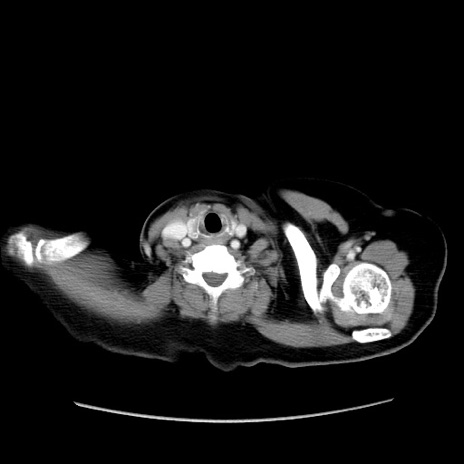

症例19(横断像)

【症例】80歳代女性

【主訴】下腹部痛

【現病歴】約8時間前より下腹部痛の出現あり、救急外来受診。

【既往歴】両側付属器切除

【身体所見】意識清明、下腹部正中に手術痕あり、その部位に一致して圧痛と反跳痛あり。腸蠕動音は亢進。

【データ】WBC 9300、CRP 0.15